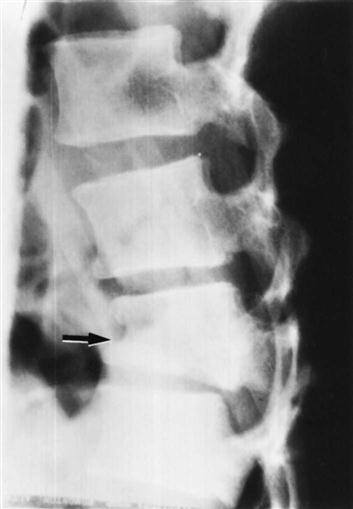

With this view (Figure 9-106), the examiner should note the following:

1. Any evidence of spondylosis or spondylolisthesis, which occurs in 2% to 4% of the population (Figure 9-107). The degree of slipping can be graded as shown in Figure 9-108.259 New grading or classification system involving lateral sacropelvic and spinopelvic balance have also been suggested.260

With the oblique view (Figure 9-110), the examiner should look for any evidence of spondylolisthesis (sometimes referred to as a “Scottie dog decapitated”) or spondylolysis (sometimes referred to as a “Scottie dog with a collar;” Figure 9-111).

In some cases, motion views may be used to demonstrate abnormal spinal motion or structural abnormalities. These are usually lateral views showing flexion and extension to demonstrate instability or spondylolisthesis (Figure 9-112), but they may also include anteroposterior views with side bending.166,262,263